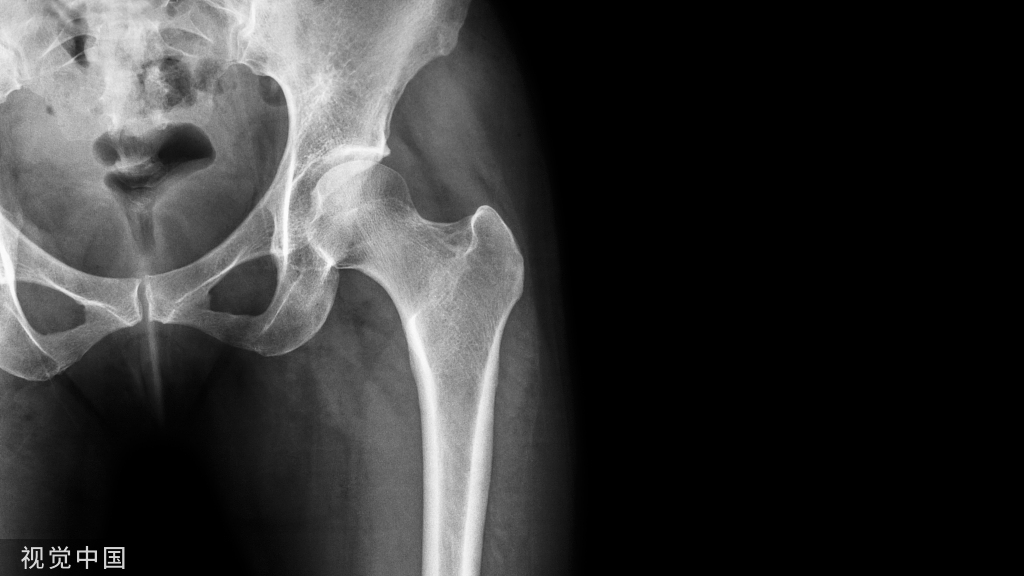

入路需根据骨折类型,还要考虑股骨头血运保护问题,以防术后头坏死(如下图)。

显露股骨头最经典的入路是前路的S-P(Smith-Peterson)或后路的K-L(Kocher-Langenbeck)。但对Pipkin骨折是选后路还是前路?尚有争议:

有人认为,Pipkin骨折走后路可直接复位关节脱位,且髋关节后脱位时后关节囊撕裂,旋股内侧动脉通过后关节囊营养股骨头的血供可能已破坏,如再走前路会切断旋股外侧动脉升支及前关节囊,进一步破坏了股骨头残存的血运;且S-P、Ganz入路的异位骨化率高。

而支持前方入路(S-P)的人认为,由于股骨颈存在前倾角,走后路即使极度内旋,也很难复位、固定前下方骨块;Pipkin骨折髋关节后脱位时不一定破坏了旋股内侧动脉及其分支,但走后路肯定会破坏股骨头血运。